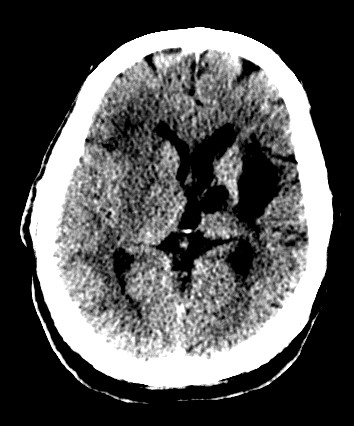

CASO 2:

Paciente con alteraciones del habla y disminución de la fuerza del brazo izquierdo. Ictus previo hace 4 años.

ASPECTS: Territorio M1 + Lenticular derecho = 10 – 2 = 8 puntos.